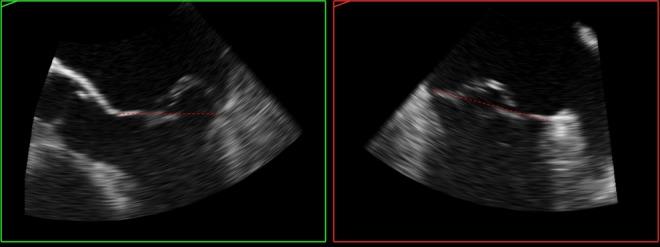

Quantitative analysis is an important part of the morphological assessment of the diseased mitral valve. It can be used to describe valve anatomy, pathology, function and the mechanisms of disease. Echocardiography is the main source of indirect quantitative data that is comparable with direct anatomic or surgical measurements. Furthermore, it can relate morphology with function. This review provides an account of current mitral valve quantification techniques and clinical applications.